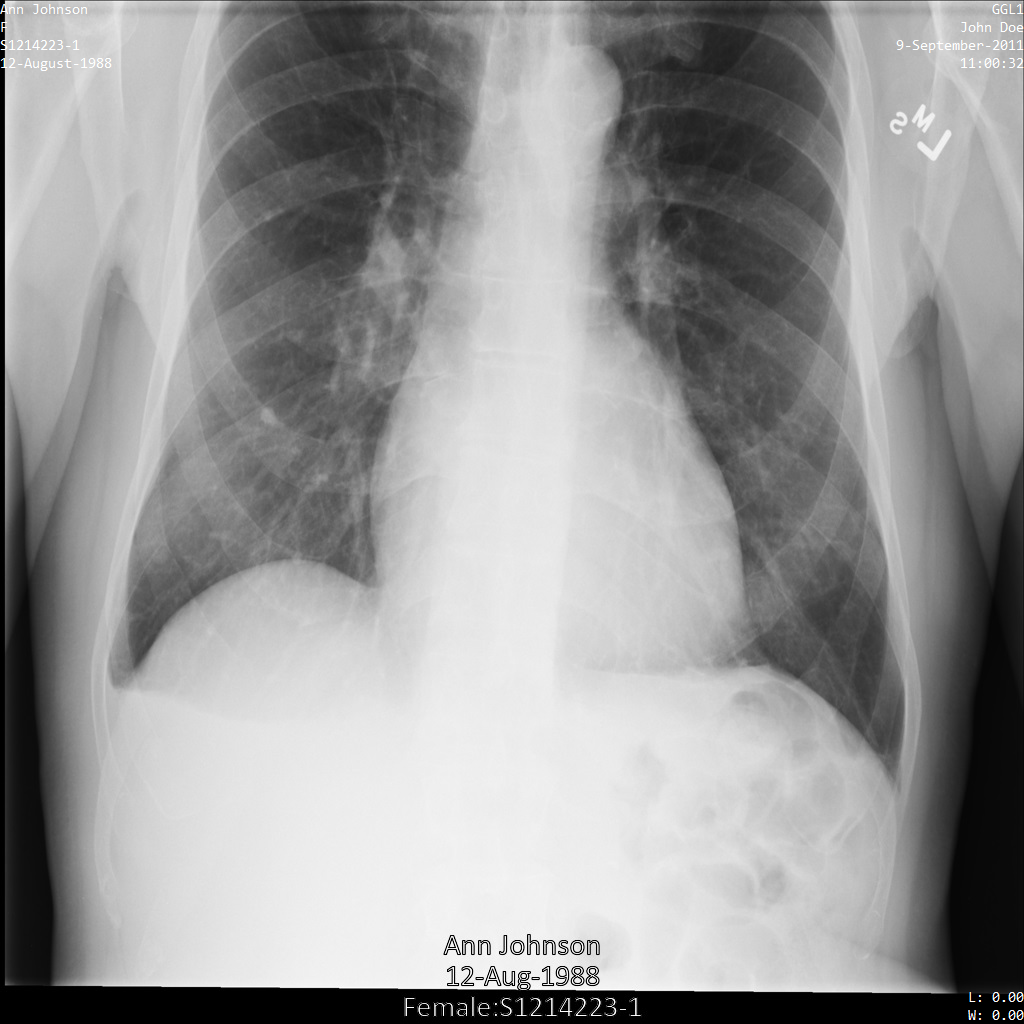

Après avoir anonymisé l'image à l'aide de REDACT_SENSITIVE_TEXT_CLEAN_DESCRIPTORS

, elle se présente comme suit. Notez que tout le texte incrusté en bas de l'image n'a pas été masqué. Le texte Female

s'affiche toujours, car PatientSex (0010,0040)

ne fait pas partie des infoTypes DICOM par défaut.

REDACT_SENSITIVE_TEXT_CLEAN_DESCRIPTORS